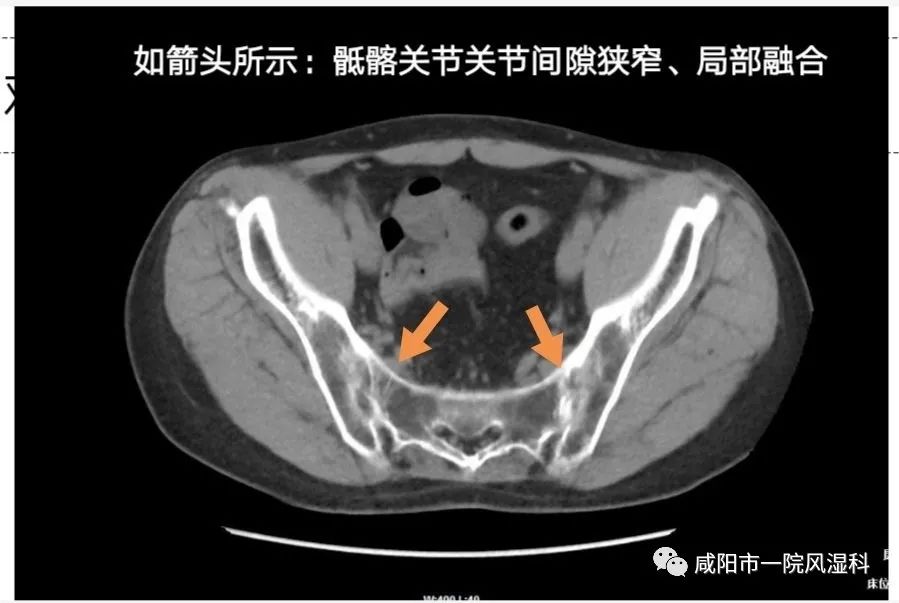

(三)中轴关节受累改变:

①骶髂关节CT受累(IV期改变)。